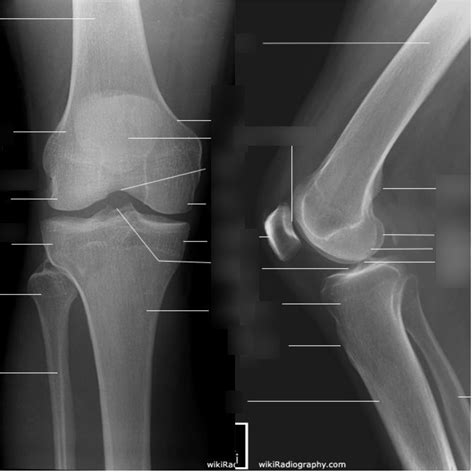

A radiologist interprets a knee X-ray by looking at several key anatomical landmarks. When a report comes back as a normal knee xray, it means the technician and radiologist have observed the following components as being within standard clinical limits:

• Bone Integrity: There are no visible breaks, hairline fractures, or bony abnormalities.

• Joint Space: The gap between the femur (thigh bone) and the tibia (shin bone) is symmetrical and maintained, which suggests that the articular cartilage has not significantly eroded.

• Alignment: The bones are in their proper anatomical position, indicating there are no major dislocations or congenital malalignments.

• Soft Tissue Shadows: While X-rays are primarily for bones, they can sometimes show swelling or fluid accumulation (effusion) around the knee joint.

Because X-rays primarily capture dense tissue, a "normal" result confirms that the structural framework of your knee is intact. This is excellent news if you were concerned about a broken bone or severe bone deformity.